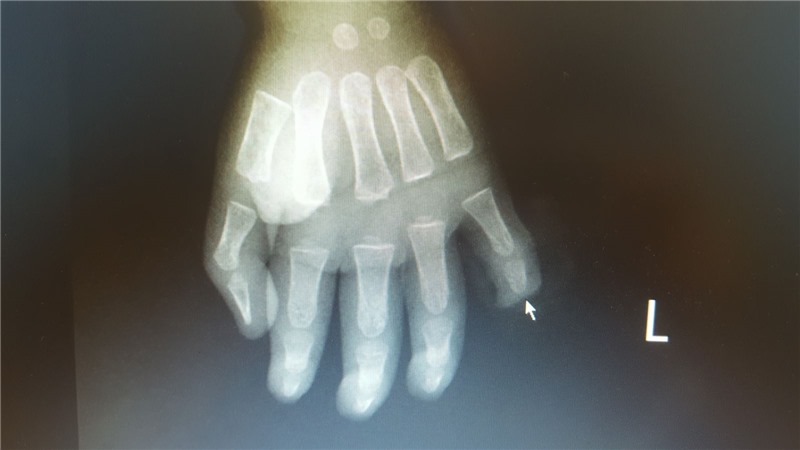

Hình ảnh phim chụp X.Quang bàn tay trái của bệnh nhi.

Bé Q. nhập viện với vết thương đứt rời đốt 3, ngón tay số 5, bàn tay trái, chảy rất nhiều máu. Các bác sĩ Khoa Chấn thương - Chỉnh hình & Bỏng đã tiến hành phẫu thuật, tạo mỏm cụt và đốt ngón tay số 5 cho bé. Hiện sức khỏe của bé đã ổn định.